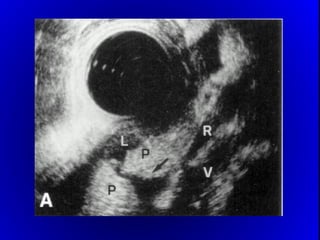

1.- FISTULOGRAMA:

 7 A 10 DIAS DE INICIADA LA FÍSTULA

 DA EL DIAGNÓSTICO ANATÓMICO.

 PRONOSTICA EL CIERRE ESPONTÁNEO O NO

2.- ECOGRAFÍA , T.A.C.

-ABSCESO INTRABDOMINAL.

-DRENAJE PERCUTÁNEO